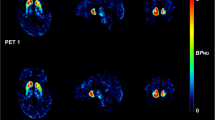

The mean SUVRs of the test and retest [18F]FP-CIT PET are summarized in Table 1. There was no significant difference in the mean SUVR between the test and retest conditions. Representative test–retest 90-min and 3-h [18F]FP-CIT PET images of ET (Fig. 2a) and PD (Fig. 2b) patients illustrate the excellent reproducibility of DAT binding in the caudate, anterior putamen, and posterior putamen. The test–retest metrics estimated using autonomic and manual methods are summarized in Tables 2 and 3, respectively. The test–retest bias (ET: range 1.05–2.04%, PD: − 0.65–2.75%) and variability (ET: 6.99–8.02%, PD: 3.51–6.94%) were both low, and reliability (ET: 0.88–0.96, PD: 0.98–0.99) was excellent. The ET group showed higher variability and lower ICCs than the PD group. In the ET group, there were no significant differences in the test–retest variability (caudate nucleus: 7.17%, anterior putamen: 6.99%, posterior putamen: 8.02%) among the subregions. However, in the PD group, the test–retest variability was significantly higher in the posterior putamen (6.94%) than in the caudate (3.51%) and anterior putamen (4.12%). The test–retest variability and ICCs of the 90-min images were similar to those of the 3-h images in both the ET and PD groups. In the ET group, the manual method showed similar test–retest reproducibility to the automatic method. However, in the PD group, the manual method (11.81%) showed higher variability than the automatic method (6.94%) in the posterior putamen.